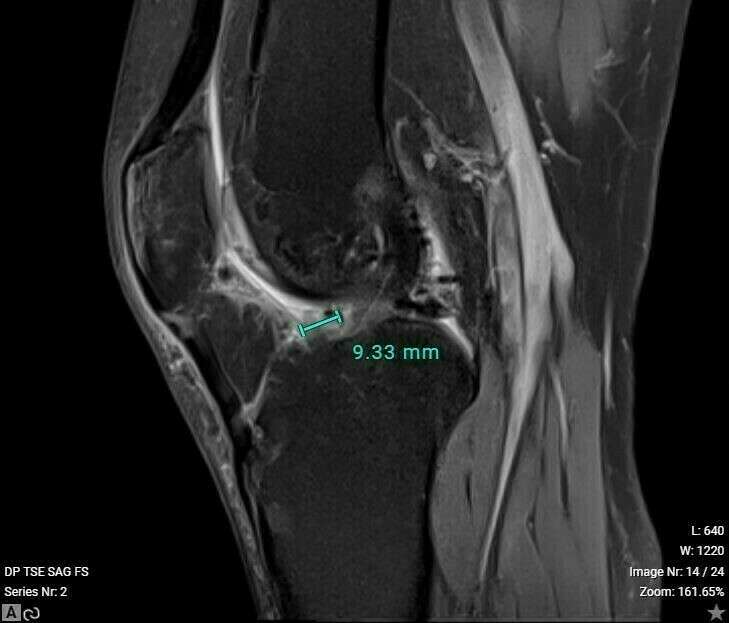

Le diagnostic de cette lésion se fait par la recherche de signes cliniques évocateurs et par l’IRM qui retrouve généralement un nodule à la face antérieure de la plastie ligamentaire au niveau de l’échancrure inter-condylienne sur lequel vient buter la trochlée fémorale.

Galerie photo